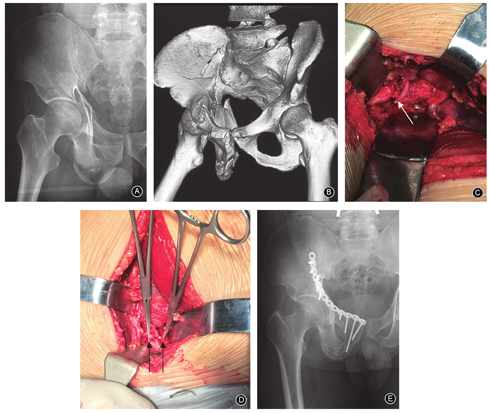

采用Stoppa入路,自脐下至耻骨联合纵行切开皮肤,深达腹筋膜,暴露腹直肌,沿腹白线钝性分离,在腹膜前间隙显露骨盆、髋臼。在耻骨联合外侧仔细探查分离鉴别"死亡冠"血管,如发现"死亡冠"血管(图1),则用游标卡尺测量该血管直径及利用软尺测量该血管行经耻骨上缘结合处至耻骨联合上边缘的距离,然后予以结扎。牵开腹直肌、髂腰肌、髂血管及股神经,屈曲髋、膝关节,充分显露耻骨联合至骶髂关节的真骨盆区域以方便骨折复位。本组11例复杂髋臼双柱骨折,由于单一Stoppa入路不能完全显露复位及固定,术中联合K-L入路进行髋臼的复位及固定。另外,4例C型骨盆骨折联合后方入路进行骨盆后环的固定。

本组52侧半骨盆中,存在吻合血管46侧(图2),无吻合血管6侧,"死亡冠"血管发生率为88.5%(46/52)。该组研究中所有"死亡冠"静脉血管直径1.8~3.7 mm,平均(2.9±0.5)mm;动脉血管直径2.4~3.0 mm,平均(2.7±0.3)mm;吻合血管经过耻骨上支的交点至耻骨联合上边缘的距离为48~71 mm,平均(56.9±5.8)mm。

46侧存在"死亡冠"血管中,8侧为动脉型,发生率为17.4%(8/46),其中位于左侧半骨盆6侧,右侧半骨盆2侧。8侧动脉型"死亡冠"血管直径2.4~3.0 mm,平均(2.7±0.3)mm;"死亡冠"血管经过耻骨上支的交点至耻骨联合上边缘的距离为54~59 mm,平均(56.8±2.1)mm。

46侧存在"死亡冠"血管中,36侧为静脉型,发生率为78.3%(36/46),其中位于左侧半骨盆20侧,右侧半骨盆16侧。36侧静脉型"死亡冠"血管直径1.8~3.7 mm,平均(2.9±0.5)mm;"死亡冠"血管经过耻骨上支的交点至耻骨联合上边缘的距离为48~71 mm,平均(57.3±6.4)mm。

46侧存在"死亡冠"血管中,2侧为混合型,即在同侧半骨盆同时存在一条动脉吻合支,一条静脉吻合支,该类型发生率为4.3%(2/46)。动脉直径分别为2.9 mm和2.1 mm,该血管行经耻骨上缘结合处至耻骨联合上边缘的距离分别为58 mm和54 mm;静脉直径分别为3.3 mm和2.6 mm,该血管行经耻骨上缘结合处至耻骨联合上边缘的距离分别为50 mm和49 mm。